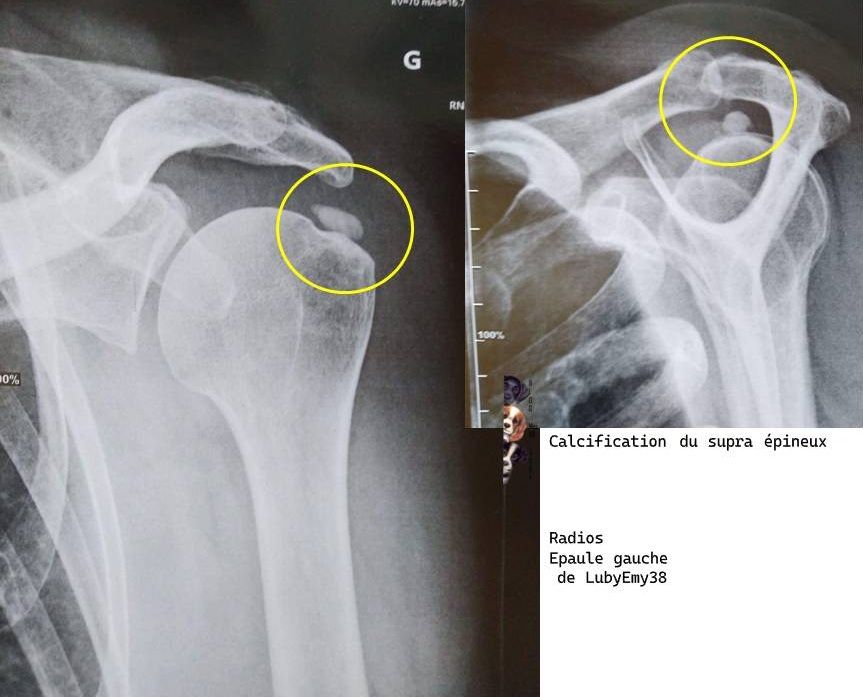

Ps : j'ai vu mon rhumato hier,

J'ai une calcification au niveau de l'épaule - à mon stade, il va falloir faire une Ponction lavage aspiration de la calcification du supra épineux sous écho ou radio (trituration)

La date d'intervention en ambulatoire est le 18/11/2025 - Petit Mari doit être avec moi, je ne pourrai conduire

rajout du 18/9 - radio de mon épaule - la grosse boule dans le rond jaune est ce qui m'embête